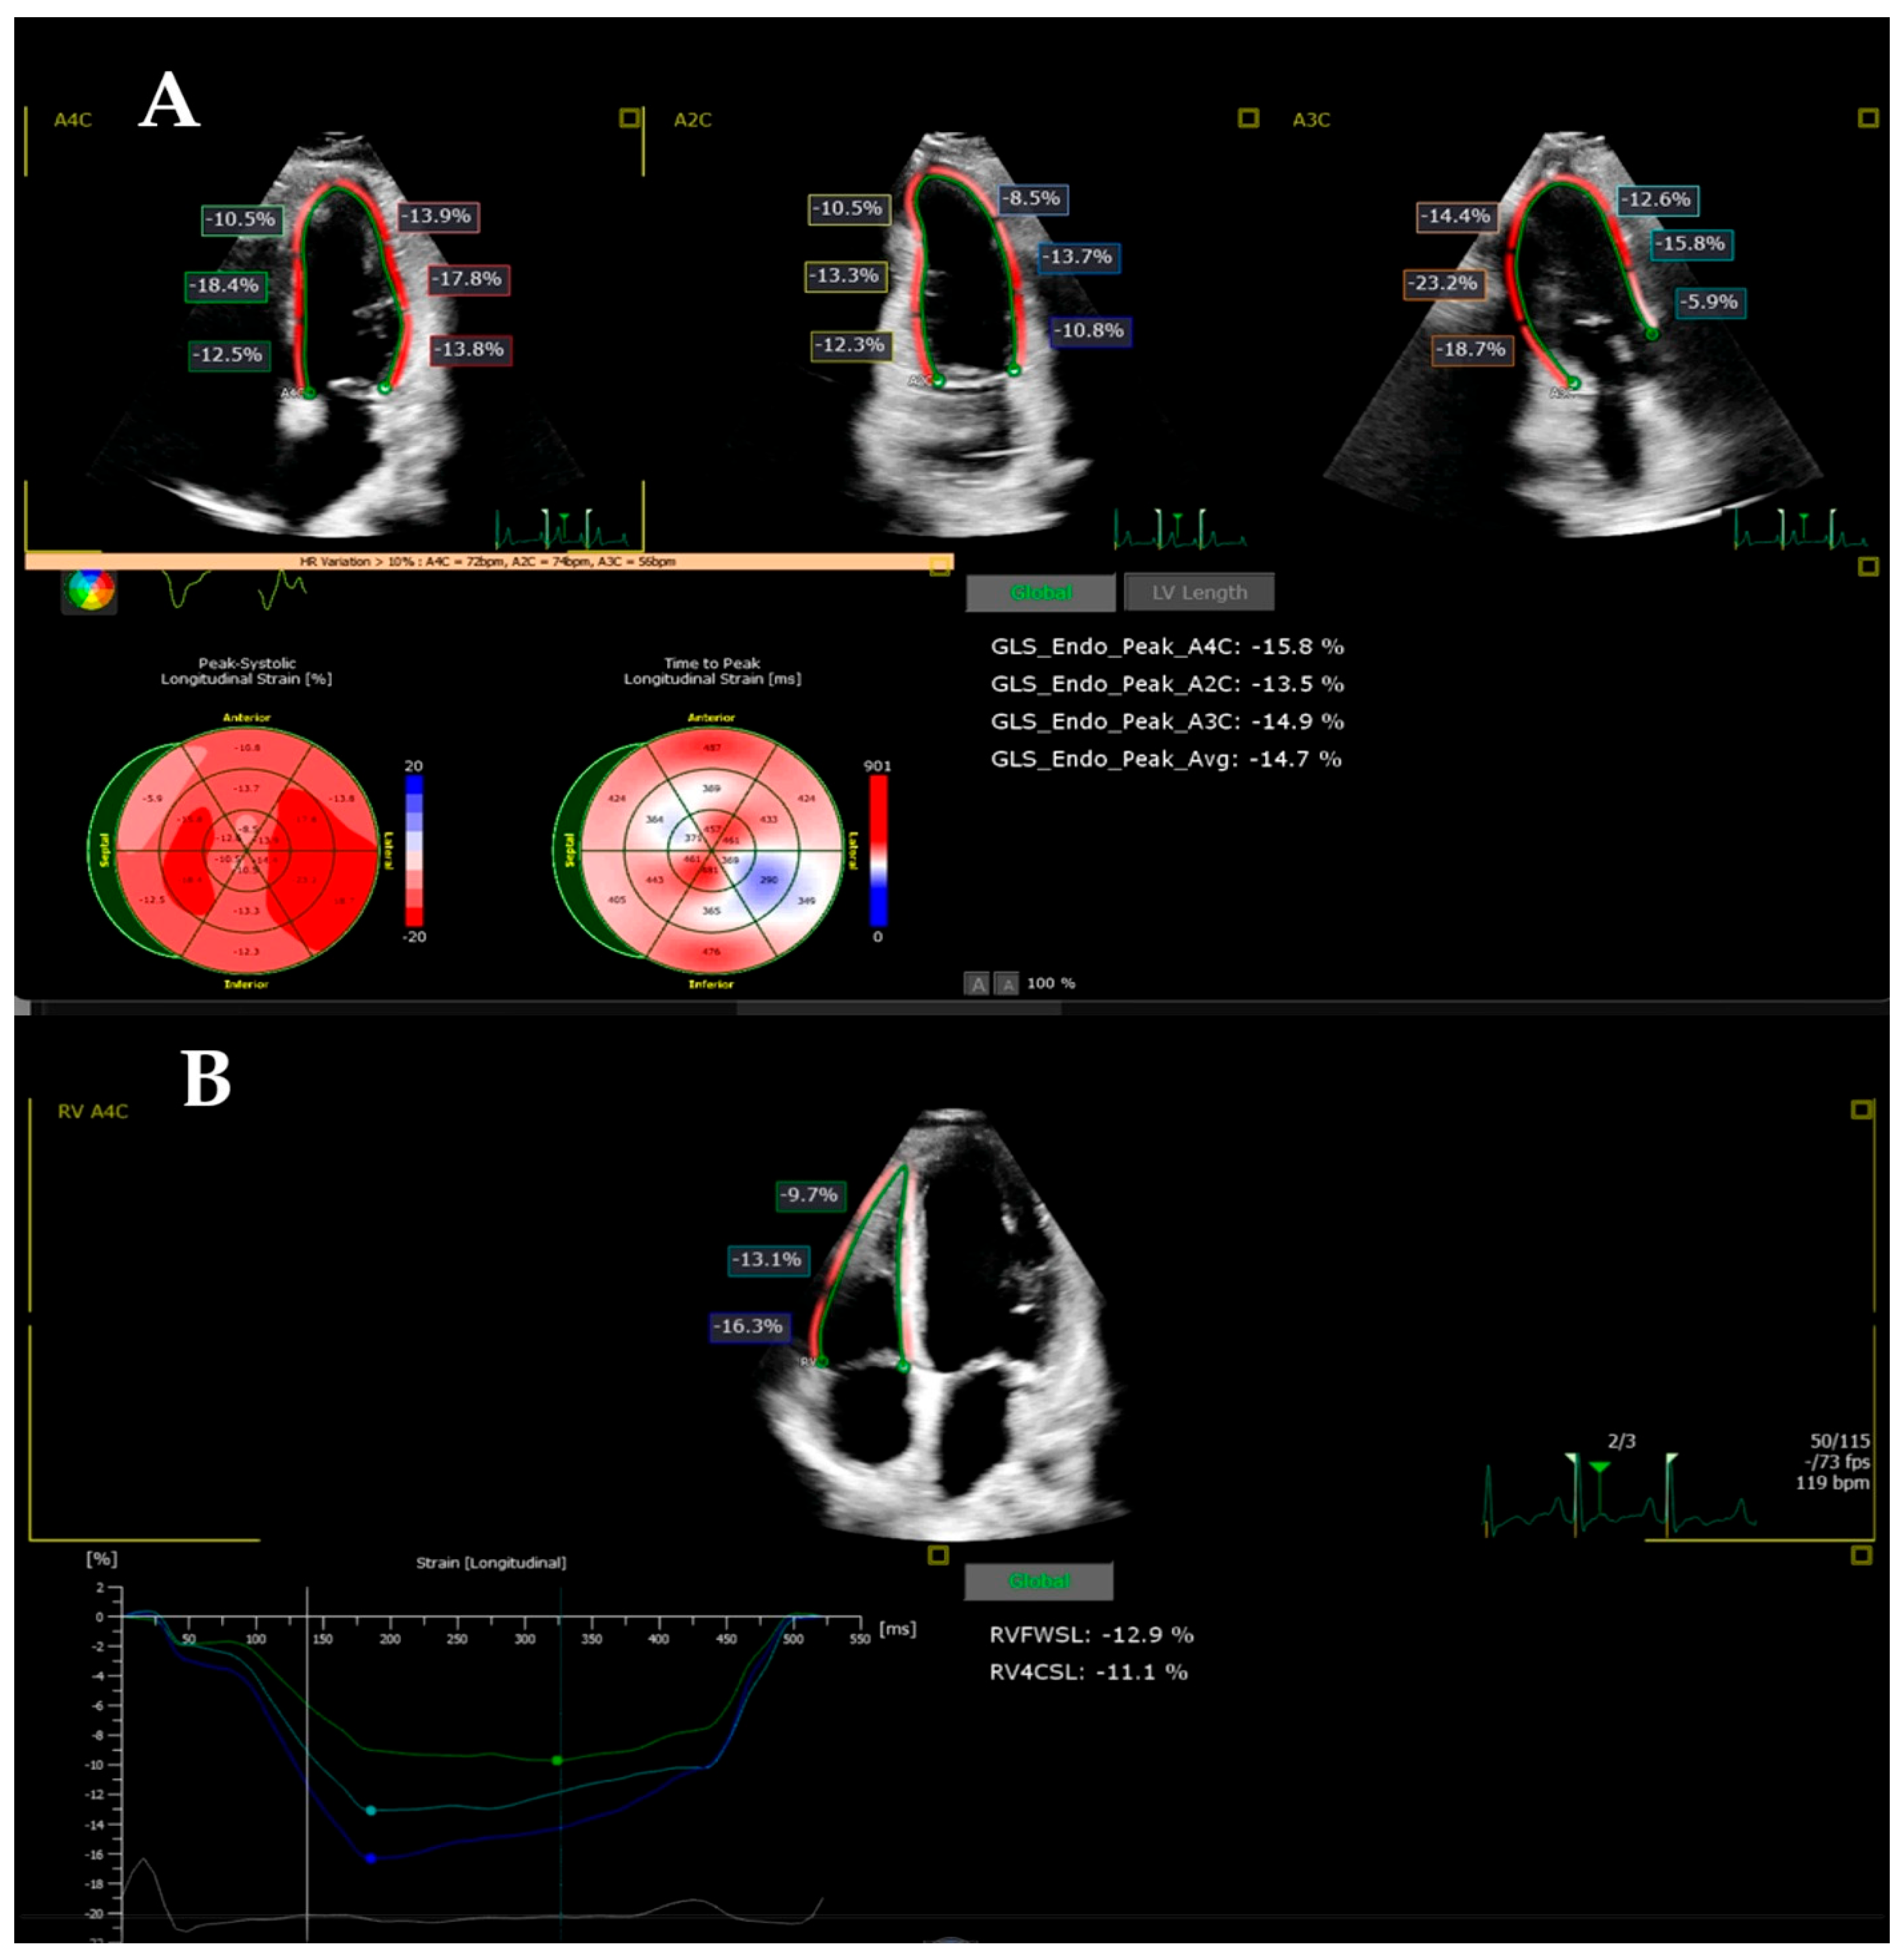

2.3. Strain Imaging

3.2. Follow-Up of the Echocardiographic Strain Indices in the MIS-C Patients (DWD Versus DD)

| LV GLS (%) | −24.23 ± 2.23 | −15.45 ± 4.76 | −20.63 ± 4.66 | 0.0001 | 0.014 | 0.0001 |

| RVFWLS (%) | −27.13 ± 13.37 | −21.94 ± 7.86 | −25.90 ± 6.76 | 0.248 | 1.000 | 0.549 |

| RV4CLS (%) | −23.90 ± 10.77 | −18.30 ± 9.90 | −21.34 ± 10.87 | 0.248 | 1.000 | 1.000 |

| BIS LS (%) | −23.51 ± 4.02 | −15.54 ± 6.39 | −19.89 ± 7.88 | 0.0001 | 0.183 | 0.077 |

| MIS LS (%) | −25.45 ± 4.10 | −16.70 ± 5.10 | −18.51 ± 9.82 | 0.0001 | 0.004 | 1.00 |

| AIS LS (%) | −25.62 ± 5.33 | −15.38 ± 5.48 | −20.66 ± 7.02 | 0.0001 | 0.024 | 0.015 |

| BAL LS (%) | −26.12 ± 5.56 | −18.19 ± 9.01 | −25.14 ± 10.45 | 0.010 | 1.00 | 0.028 |

| MAL LS (%) | −22.13 ± 3.85 | −15.45 ± 5.08 | −18.83 ± 6.05 | 0.0001 | 0.151 | 0.136 |

| AAL LS (%) | −25.20 ± 4.86 | −15.26 ± 4.90 | −19.30 ± 4.99 | 0.0001 | 0.001 | 0.025 |

| BRV LS (%) | −33.55 ± 5.32 | −23.85 ± 7.91 | −27.72 ± 8.43 | 0.0001 | 0.032 | 0.259 |

| MRV LS (%) | −28.68 ± 4.55 | −21.11 ± 7.55 | −24.99 ± 6.83 | 0.001 | 0.187 | 0.15 |

| ARV LS (%) | −26.24 ± 4.55 | −18.59 ± 10.26 | −23.64 ± 7.50 | 0.005 | 0.819 | 0.107 |